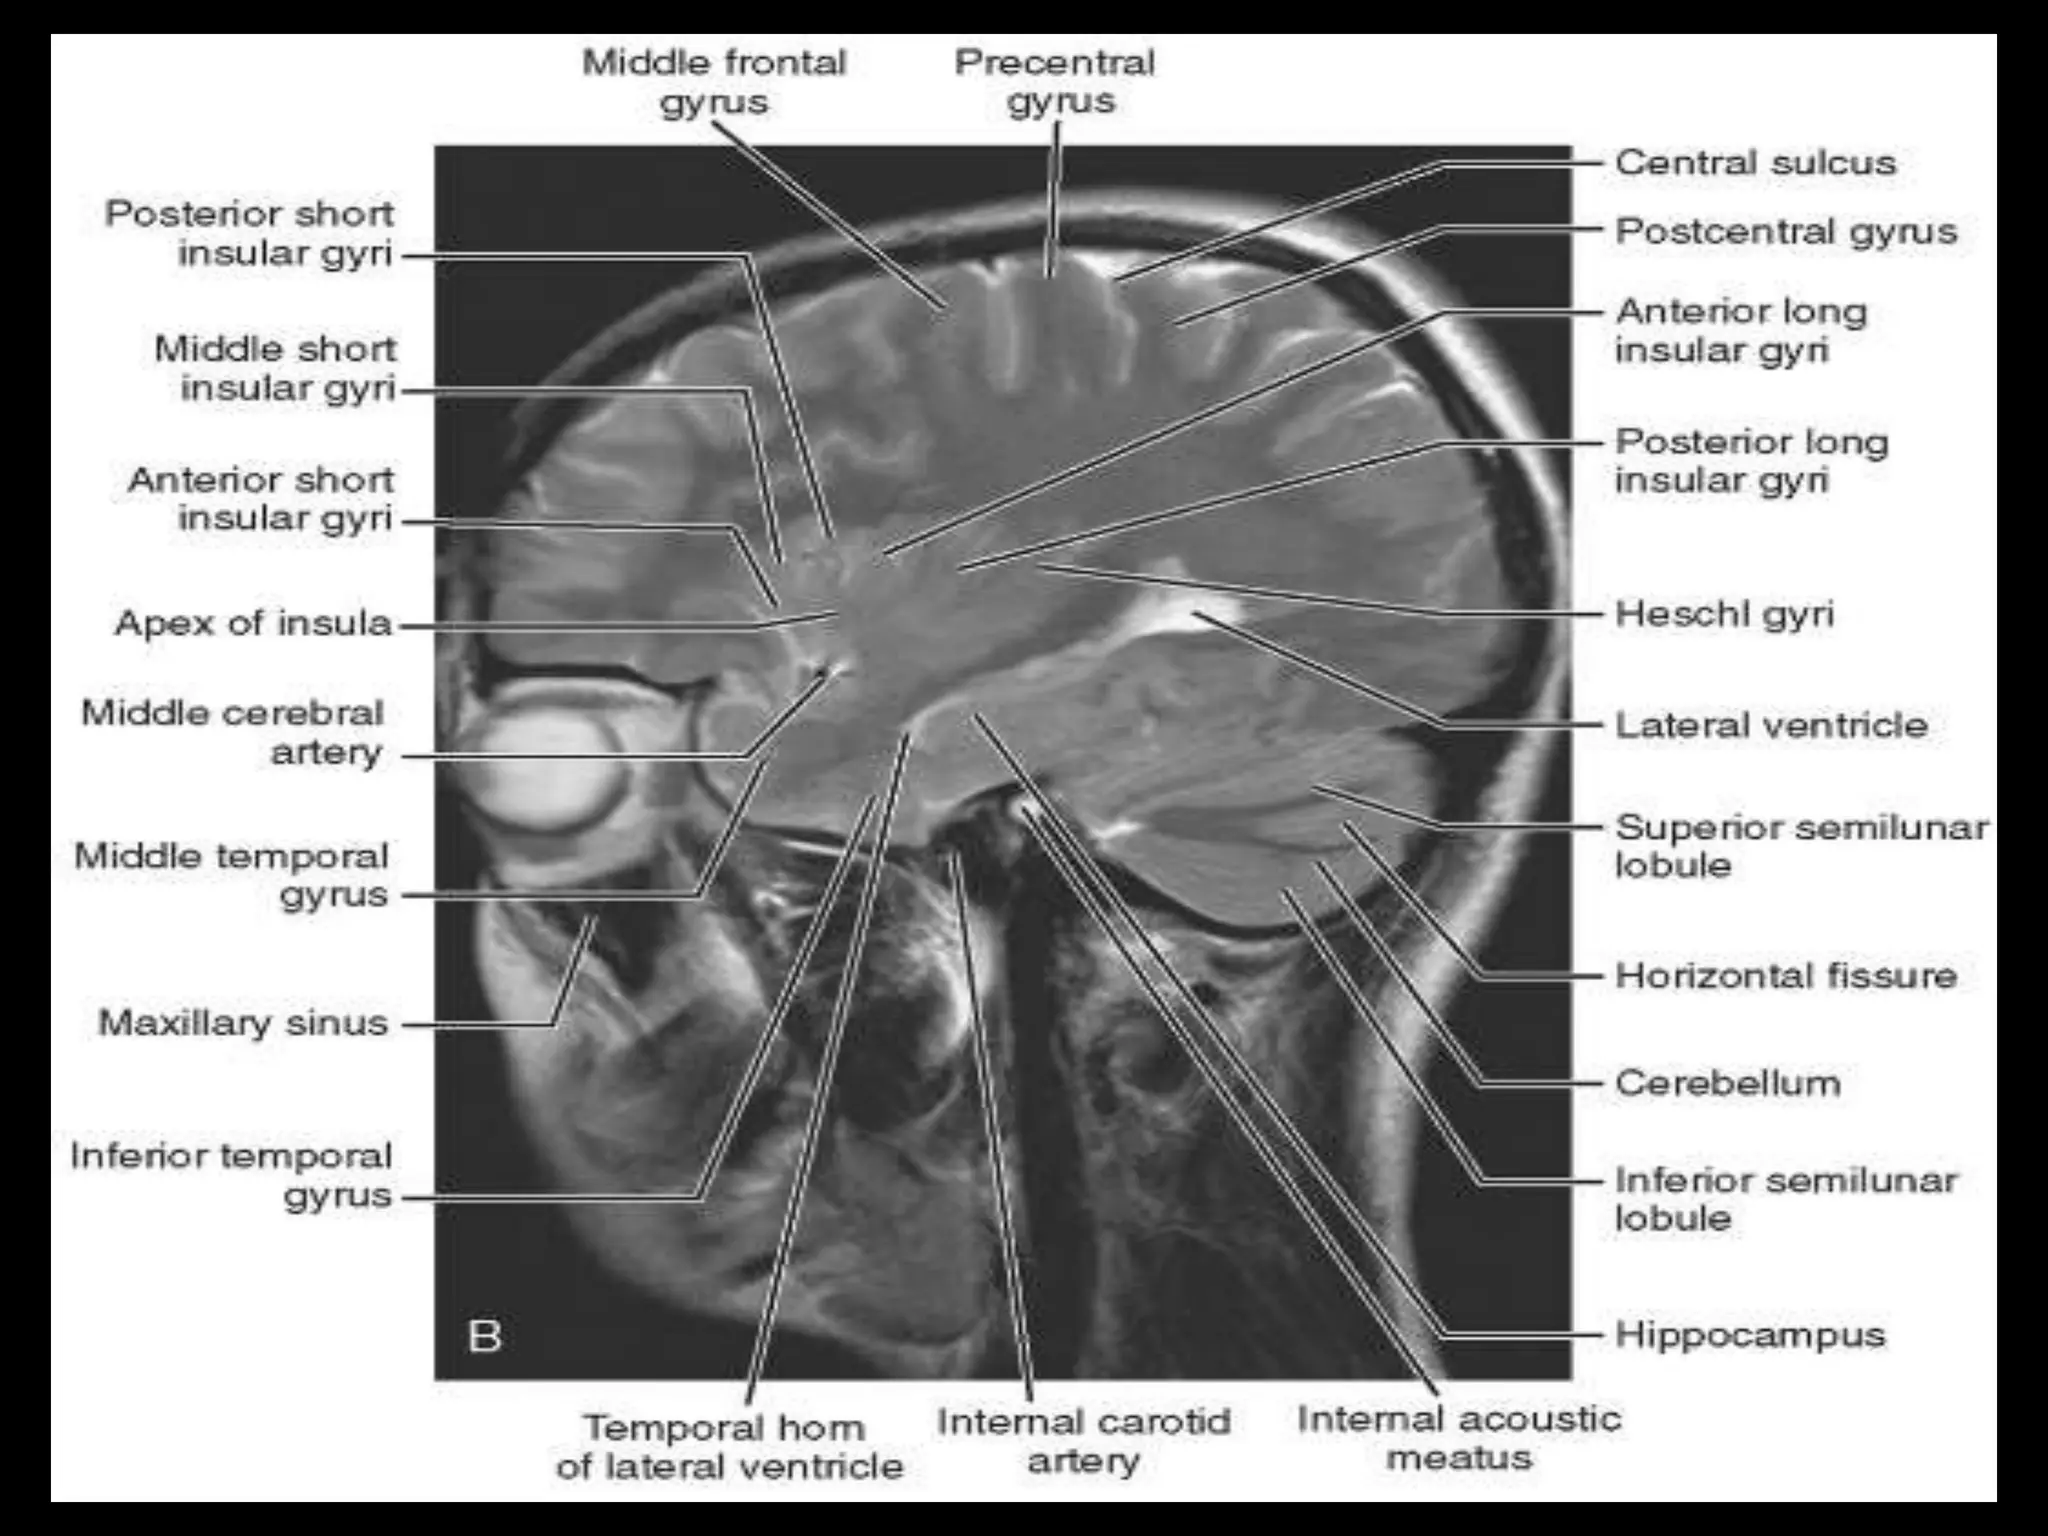

The two cerebralhemispheres are separated by interhemispheric fissures and falx cerebri. On the lateral surface of the brain, the sylvian fissure (lateral fissure) and the rolandic fissure (central fissure) separate the cerebral hemisphere into the frontal lobe, temporal lobe, parietal lobe, and a line drawn from the parieto-occipital sulcus onto the preoccipital notch, delineating the boundaries of the parietal and temporal lobes from that of the occipital lobe. The frontal lobe, the largest of all the brain, has four principal gyri: the precentral gyrus and the superior frontal, middle frontal, and inferior frontal gyri. The precentral gyrus, parallel to the central sulcus, together with the anterior bank of the central sulcus, comprises the primary motor area, which is one of the most important cortical areas for movement. Rostral to the precentral sulcus is the premotor area, another important area for movement. The middle frontal gyrus contains Brodmann’s area 8, known as the frontal eye field, which is important for conjugate eye movements. Another important motor area for speech called Broca’s area, is located at the triangular and the opercular parts of the inferior frontal gyrus in the dominant hemisphere.

In the parietallobe, there are a postcentral gyrus, a superior parietal lobule, and an inferior parietal lobule. The postcentral gyrus is a primary somesthetic area involved in general body sensation. In the temporal lobe, the superior, middle, and inferior temporal gyri are separated by the two transverse sulci. The posterior fossa contains the cerebellum and brain stem. The posterior fossa is outlined by the clivus and petrous bones anteroinferiorly, the tentorium cerebelli superiorly, and the occipital bone posteroinferiorly. The cerebellum is located posteriorly in the two thirds of the posterior fossa, separated from the brain stem by the fourth ventricle. The brain stem occupies the anterior third of the posterior fossa, including the midbrain, pons, and medulla oblongata. The brain derives its vascular supply via two carotid and two vertebral arteries. The internal carotid artery bifurcates terminally into the anterior and middle cerebral arteries. The two vertebral arteries unite at the caudal border of the pons to form the basilar artery.